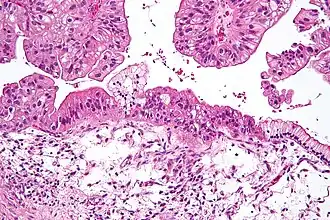

Муцинозная опухоль яичника низкого потенциала злокачественности. Среднее увеличение, окраска гематоксилин-эозином.